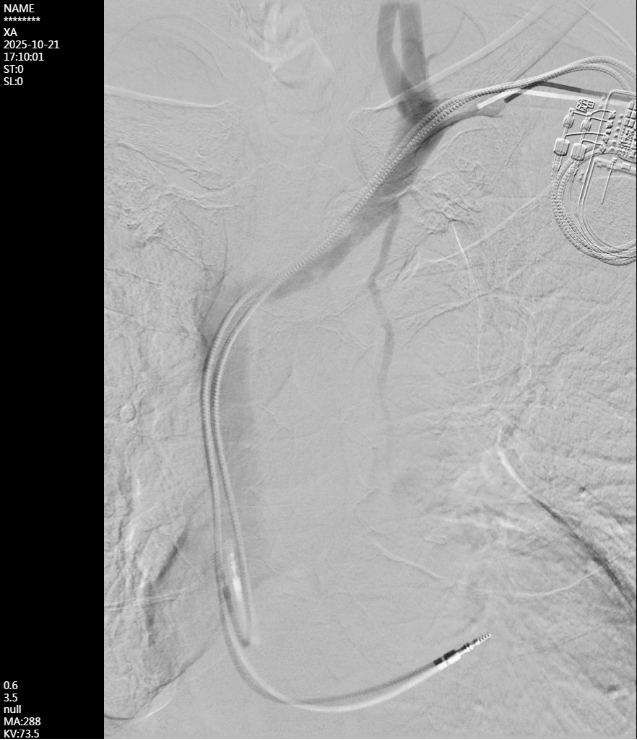

手术团队选取左上臂肱动脉-贵要静脉内瘘的贵要静脉段,距肘关节3cm处为穿刺点,置入血管鞘管。DSA造影显示左侧头臂静脉(无名静脉)闭塞,周围大量侧支循环开放,锁骨下静脉及腋静脉未见狭窄。术中,经造影导管置入0.035英寸超滑导丝,在闭塞处受阻,后更换为0.018英寸导丝,在造影导管引导下成功通过闭塞段,进入上腔静脉并送达下腔静脉。随后更换加硬导丝,以不同型号球囊由小到大逐级、缓慢扩张左侧头臂静脉及与上腔静脉交汇处,最终成功解除狭窄。术后DSA显示左头臂静脉恢复通畅,侧支血管影消失,全程起搏器功能正常。

成功开通闭塞的左侧头臂静脉,全程心脏起搏器功能良好。